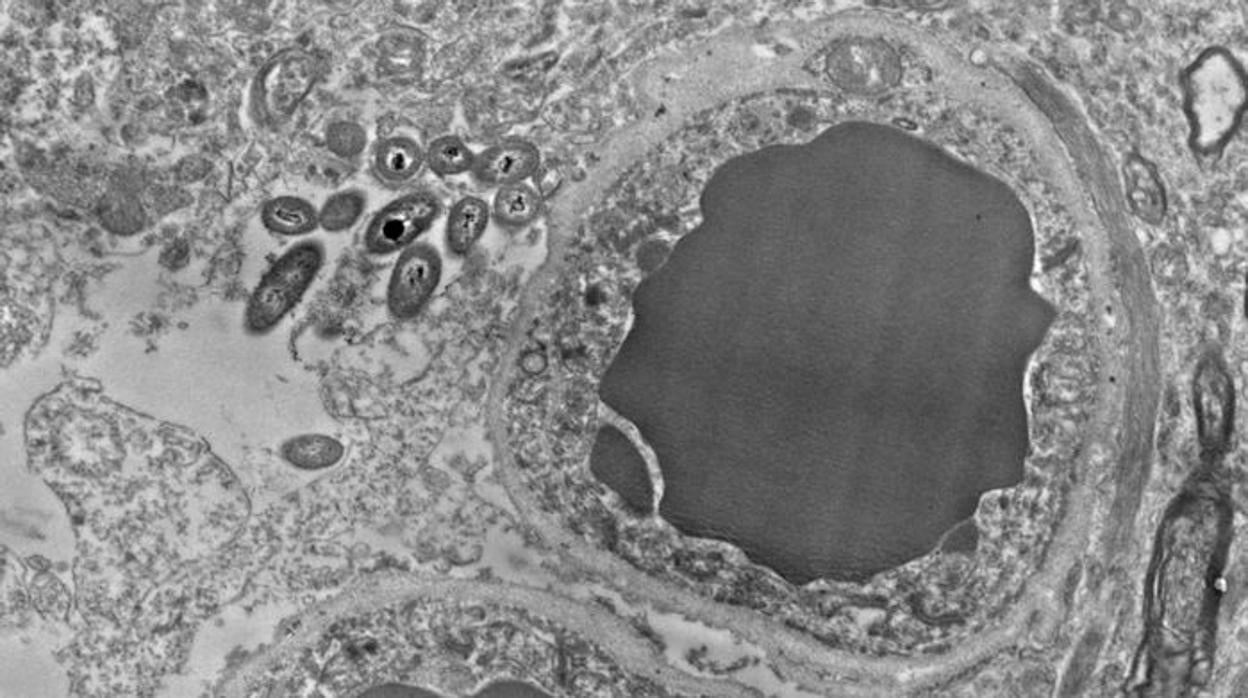

Iniciar sesiónEl cerebro siempre se ha considerado como un entorno estéril. Está protegido por la barrera hematoencefálica, un conjunto de «filtros» situados en los vasos sanguíneos que evitan la entrada de patógenos, toxinas y otras moléculas. Pero, recientemente, un grupo de investigadores de la Universidad de Alabama en Birmingham ... (EE.UU.) examinaba muestras de cerebros cuando encontró por casualidad unas formas alargadas en su interior . Las posteriores observaciones mostraron que esos puntos son bacterias que pertenecen a tres grupos de microbios que se suelen encontrar en el intestino. Por ahora, las investigaciones no permiten descartar que dichas bacterias entraran en las células cerebrales a causa de una contaminación, pero sugieren que podría haber bacterias intestinales viviendo dentro del cerebro de personas sanas.

El decubrimiento fue totalmente accidental o, tal como ha recordado la investigadora, toda una serendipia. Junto a ella, las científicas Courtney Walker y Charlene Farmer trabajaban con muestras de cerebro extraídas de 34 personas fallecidas solo unas horas antes. Su objetivo era comparar los cerebros de enfermos de esquizofrenia con los de personas no afectadas por esta dolencia. Las fotografías de microscopía electrónica, en las que se extraen pequeñas láminas de tejido que se fijan a través de complejas técnicas, revelaron la presencia de corpúsculos dentro de ciertas células y en zonas concretas de estas.

«Encontramos las bacterias predominantemente en dos o tres lugares», ha explicado Roberts. En concreto, en los pies de los astrocitos, en la barrera hematoencefálica y junto a axones mielinizados. Además, la presencia de los microbios varió en cada región cerebral. En general, resultaron ser más abundantes en la sustancia negra (implicada en movimiento de ojos, planificación de movimientos, aprendizaje y adicción), el hipocampo (memoria, entre otros procesos) y el córtex prefrontal (pensamiento, memoria a corto plazo, atención), y más escasas en el cuerpo estriado (función motora, recompensa, etc).

Además, y según ha detallado Rosalinda Roberts, en los ratones, pero no en los humanos, observaron bacterias dentro de los de los núcleos de las neuronas . También las vieron en las cercanías de los axones mielinizados.